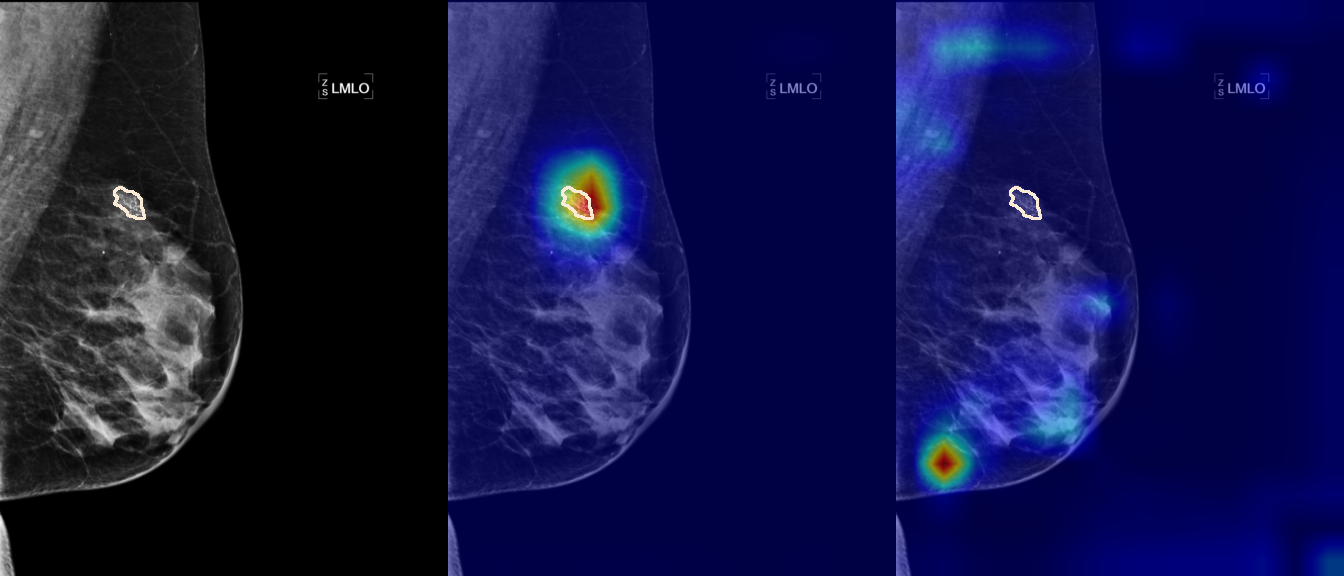

To interpret the decision-making process behind the quantitative results, we visualized Class Activation Maps (CAM) for the top-performing methods, ERM and VREx. Figures 1 through 2 illustrate discriminative regions identified by the models within the full mammograms.

Localization of Clinical Features: A key concern in medical AI is whether high performance stems from genuine pathology detection or spurious background correlations. Our visualizations suggest that Standard ERM achieves its superior quantitative performance by predominantly prioritizing clinical cues. As shown in the top rows of the Figure 1 and Figure 2, the ERM-trained models consistently focus attention on the specific lesion regions within the breast tissue. This demonstrates that despite lacking explicit invariance constraints, ERM is capable of learning robust, medically relevant features when trained on diverse multi-source data.

Attention Drift in Both Methods: While both ERM and VREx generally identify the correct region of interest in successful cases, neither method is immune to attention drift. We observe instances in both training paradigms where the model focuses on irrelevant areas, such as healthy fibroglandular tissue or background artifacts (e.g., rows 5 and 6 in Figure 1). This indicates that while VREx is designed to penalize instability, it does not guarantee perfect anatomical focus compared to the unconstrained ERM baseline.